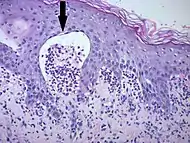

| Mycosis fungoides | Present | Focal | Regular or irregular | Normal | Normal | Minimal or no spongiosis; ±Pautrier microabscess | Atypical lymphoid cells lining the dermo–epidermal junction |  Pautrier microabscesses |